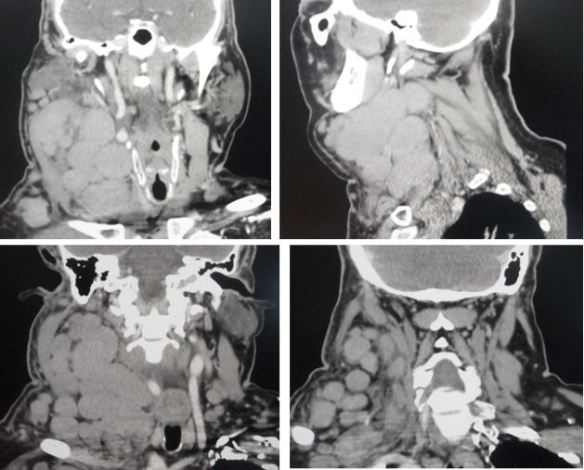

This 71-year-old lady was diagnosed with lymphoma and breast cancer. She underwent three rounds of chemotherapy (total of 24 cycles over a period of time). The treatment failed. Her health deteriorated. The family had to sell a house just to pay for the medical bills. At a loss, the family sought our help. The patient was started on our therapy. Her health improved! For sure, there is no need to sell another house to pay for this herbal treatment!